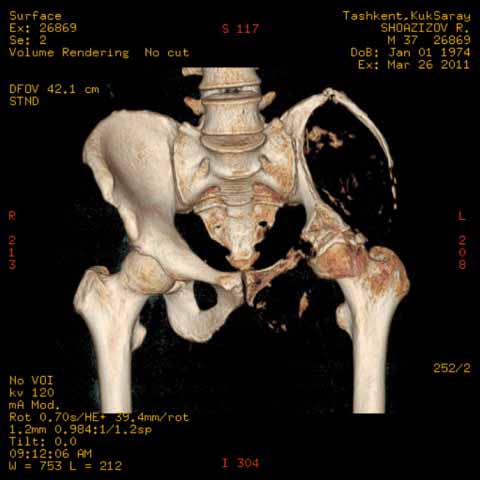

Могу пока выложить еще снимки и показать хронологию данного процесса и его прогрессирование, первый снимок был 2011 года. Вот этот 2009

Также структуру поражения кости можно увидеть на обычных рентгенограммах таза или Компьютерно-Томографических срезах. Трехмерные снимки, кроме красивой картины, не добавляют информации, и самым главным информативным является МРТ, которая покажет структуру ячеек.